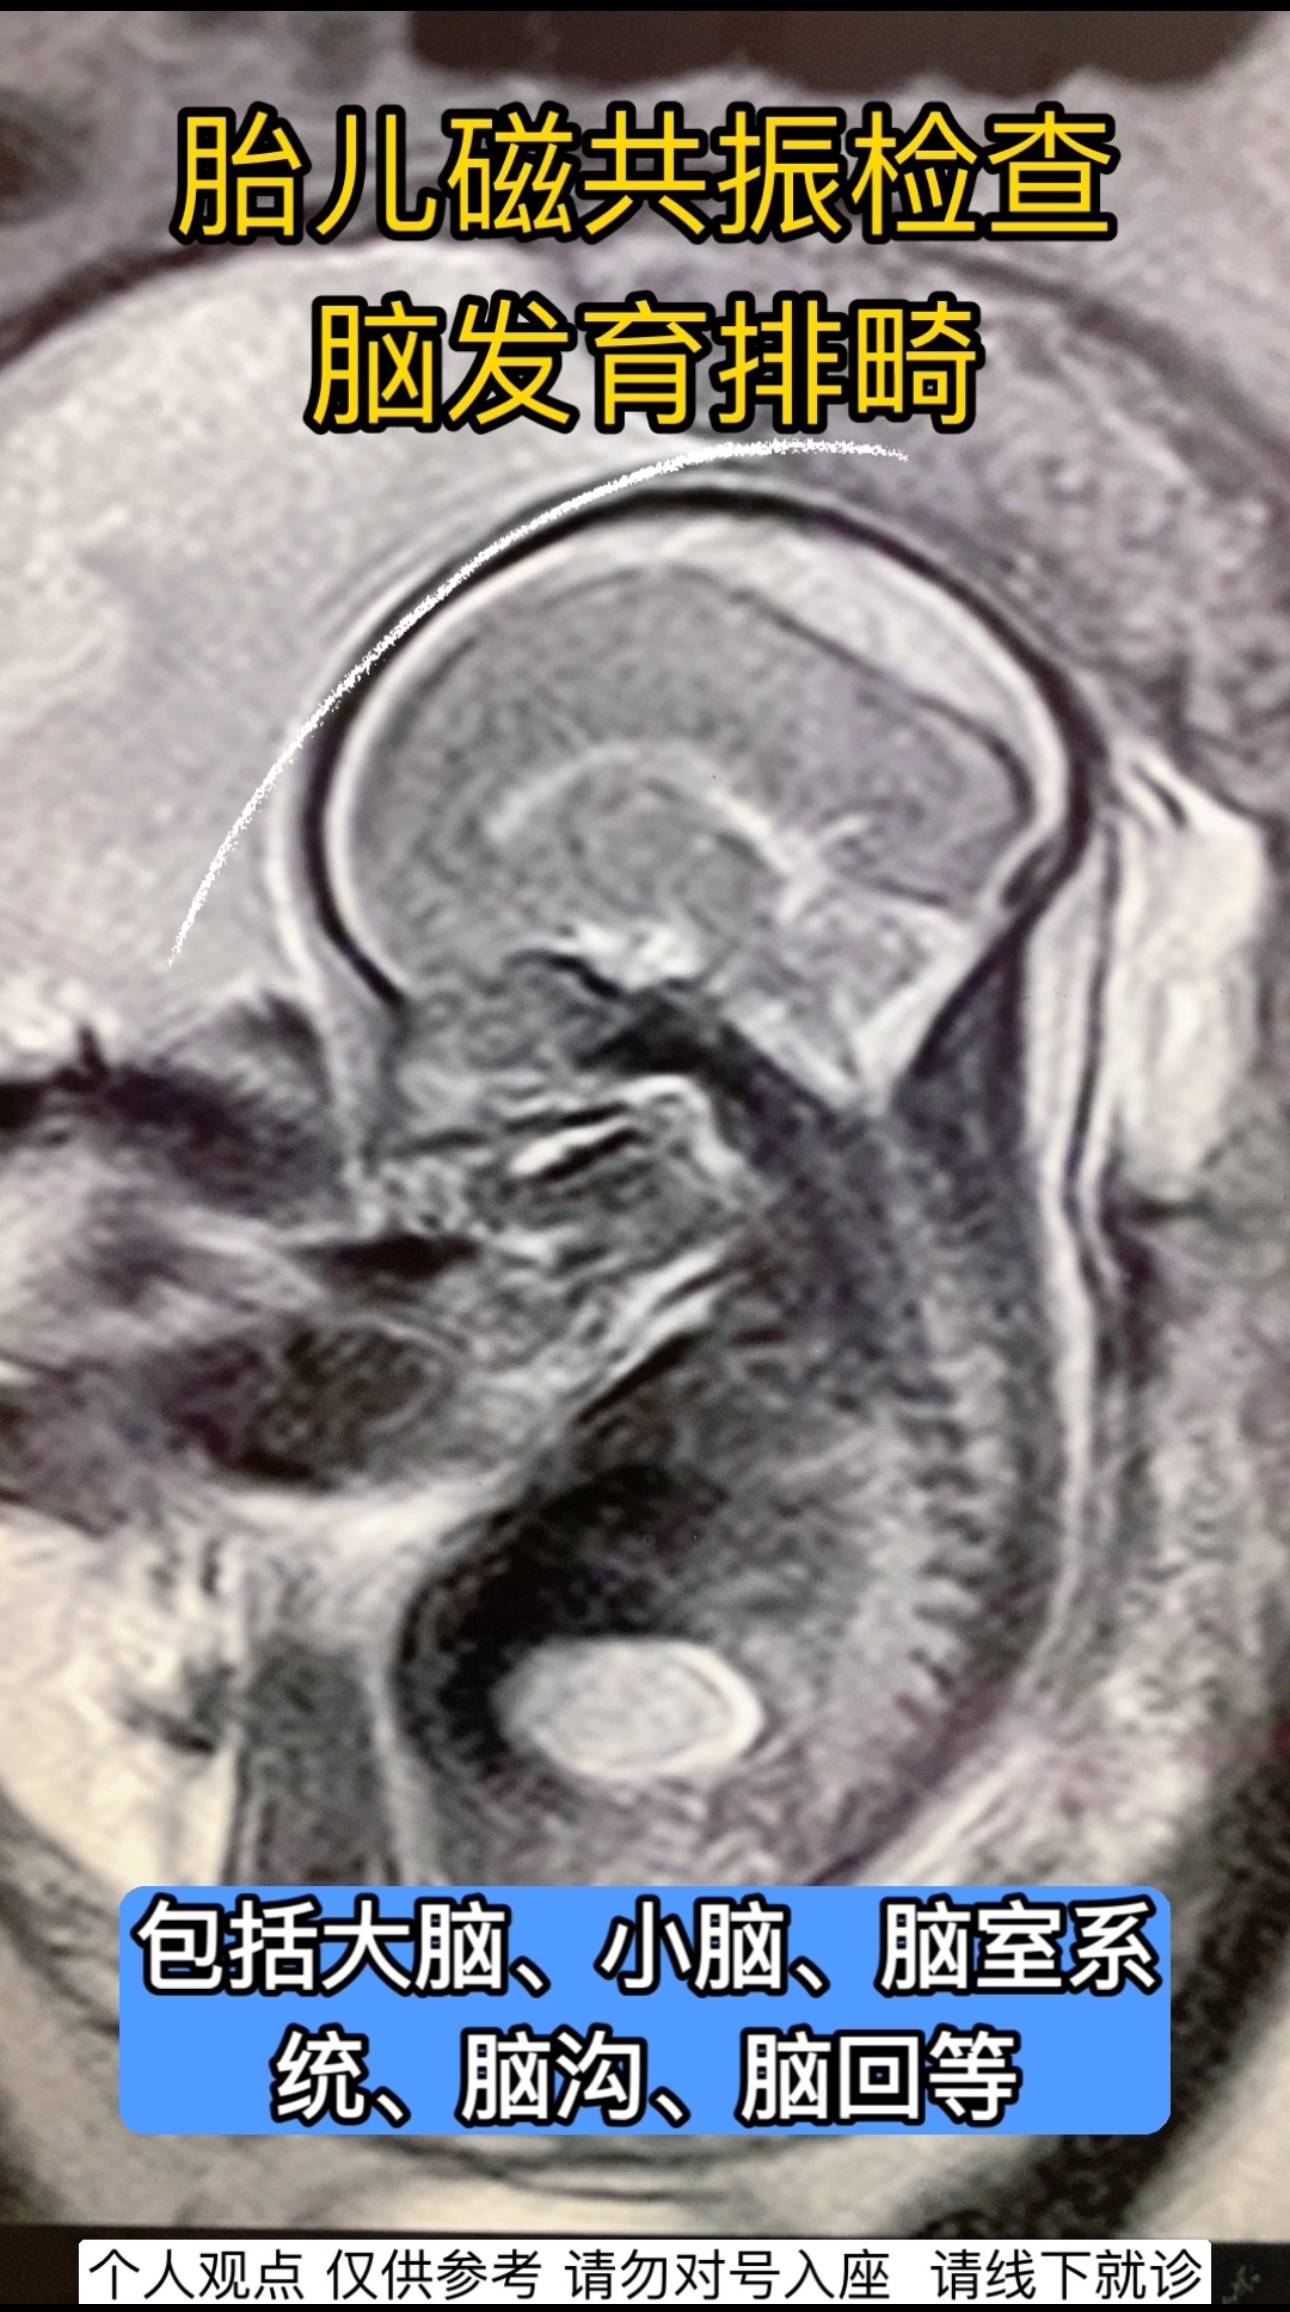

主要用于更详细地观察胎儿头颅的结构,包括大脑、小脑、脑室系统、脑沟、脑回等,辅助诊断胎儿是否存在脑部发育异常,如先天性脑畸形、脑积水、脑肿瘤、脑出血等。

具有良好的软组织分辨力,能多方位、多序列成像,可更全面、准确地显示胎儿脑部的细微结构和病变,弥补超声检查的不足。对一些超声难以发现或诊断不明确的脑部病变,能提供更详细的信息。